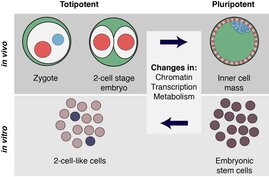

Totipotenz wird für die Forschung und künftige medizinische Anwendungen immer wichtiger und das Interesse an effizienten Methoden, um…